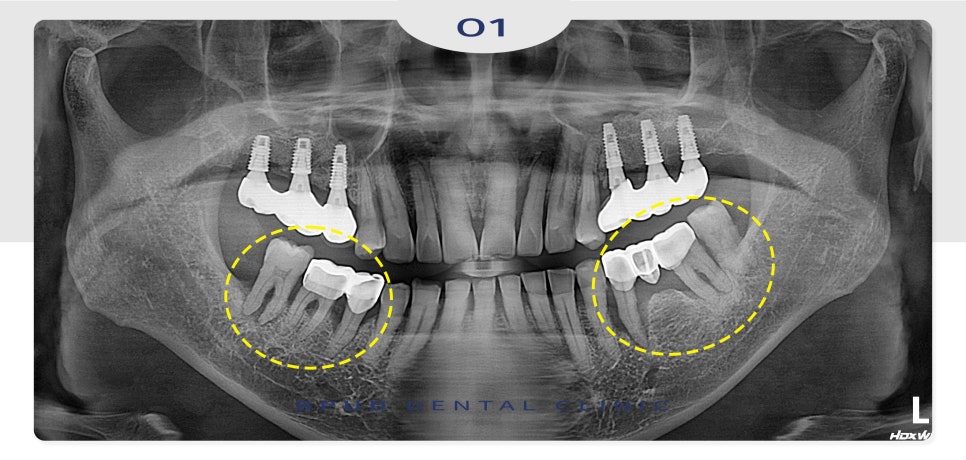

환자분께서는 처음 내원 당시

아래쪽의 치아들이 많이 흔들리고

상태가 좋지 않아 치료 상담을 위해

내원을 해주셨는데요.

처음 내원 당시부터 위쪽 임플란트가

좋지 않음을 설명드리고 주기적인

경과 관찰이 필요하다고 말씀을 드렸는데요.

그러나 오랜 기간 방치로 인해

약 2년 후, 주변에 뼈가 심각하게 소실되어

결국 상악동 내부로 임플란트가 빠져버린 채로

재내원해 주셨습니다.